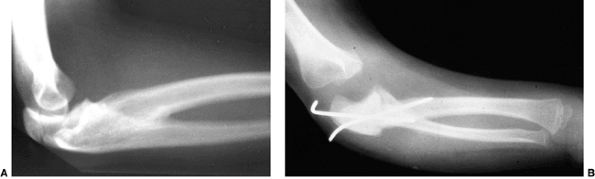

![]() |

Figure 23.7

Lateral radiograph of congenital posterolateral dislocation of the radial head. There is evidence of tapering of the radial head and neck posteriorly, bowing of the ulna posteriorly, and a small dome-shaped radial head. These patients often have limited elbow extension and develop intraarticular pain at the abnormal radiocapitellar articulation in adolescence. |